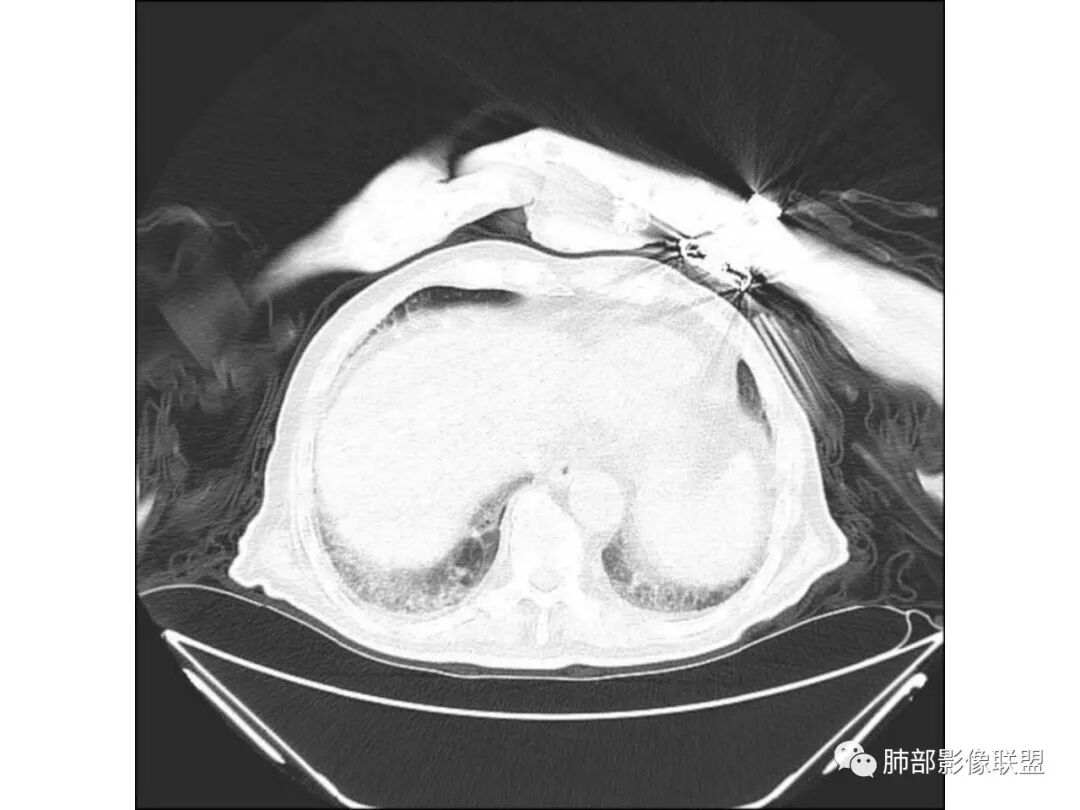

毛勤香:

老年男性,糖尿病患者,右肺上叶大片状影伴多发小空洞和支气管充气征,有重力分布趋向,播散灶不明显,两肺胸膜下多发慢性炎症改变,有肺气肿肺大疱背景,肺门纵膈多发小淋巴结,少许钙化,急性起病,首先考虑感染性病变,1.气肿性肺炎?2.肺克?建议结合临床相关实验室检查,影像学角度常规治疗后复查除外粘液腺癌可能。右肺上叶一空洞内见结节影,考虑合并曲菌感染,干酪性肺炎可以,主要没有播散灶,结核待排吧

老年男性,咳嗽气喘10天,双肺明显肺气肿,右上肺叶实变,内见大量空洞及囊腔样改变(部分为支气管扩张),实变区周围表现为网格样改变,有明显的小叶间隔增厚,边界似清非清,支气管走行僵硬,有枯树枝样改变,双下肺胸膜下小叶间隔增厚明显,边缘相对模糊,综合考虑如下:1、粘液腺癌可能大(枯树枝样改变,边界似清非清,小叶间隔增厚符合)。2、结核,右上肺似像干酷样改变,内有空洞及支扩样改变支持,但下肺及左肺无相关支气管播散的小叶中心结节及树芽,不支持,临床病症不支持,只有咳嗽,喘气,无咳痰及结核中毒症状。当然结核是妖,需要结合痰检及结核相关指标进一步明确。3、肺克,虽有10年糖尿病史,但肺部只有右肺改变明显,无胸膜下脓肿表现,无脓毒栓表现,临床症状也不支持。4、其他感染?双下肺胸膜下病灶边缘模糊,不完全除外,需要结合临床炎性指标分析。

宇宙星空:

右上肺大片状高密度影,呈蜂窝样改变,部分气腔无壁,部分呈厚壁改变,内部结构紊乱,部分边缘GGO边界清楚,大小不一,病灶近端小远端大,近端支气管壁增厚,支持感染性病变,考虑结核,其内支气管呈枯树枝改变,病灶局部膨隆,内部结构紊乱,边界的GGO部分清楚,恶性(腺癌)待排。

纤维化收缩比较明显(其内支气管受牵拉扩张、小叶间隔增厚也受牵拉)虫噬样或蜂窝样改变

南边:

总体分析就是不符合恶性。蜂窝、空洞与肺气肿有关,支气管主要还是远端稍扩张